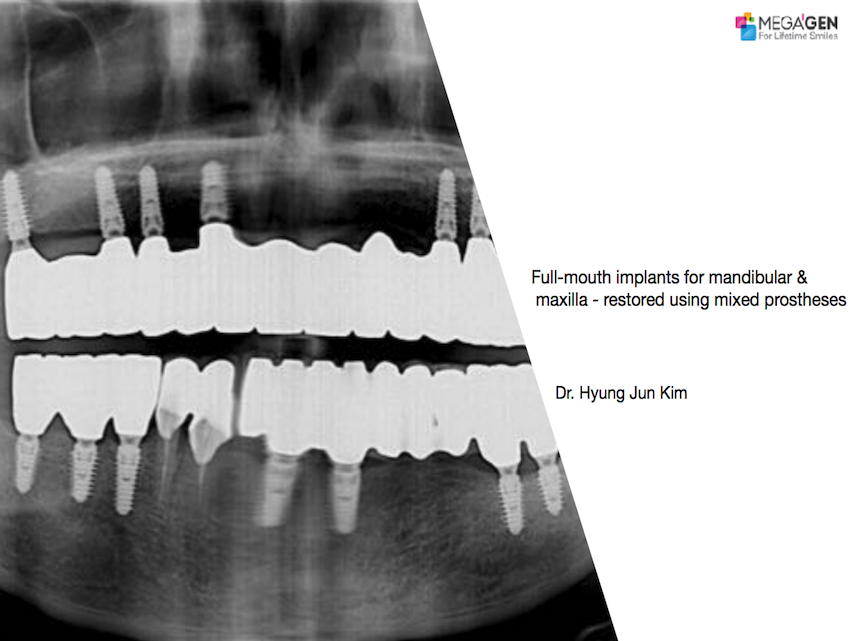

Full-mouth implants for mandibular & maxilla – restored using mixed prostheses

#12,#15,#17,#22,#25,#27,#32,#37,#41,#45,#47,AnyRidge,Biological stability,Dr. Hyung Jun Kim,Edentulous,Full-mouth implants,Full-mouth rehabilitation,Immediate Placement,Long-term clinical case,Mandibular Anterior,Mandibular Posterior,Maxillary Anterior,Maxillary Posterior,Octa abutment